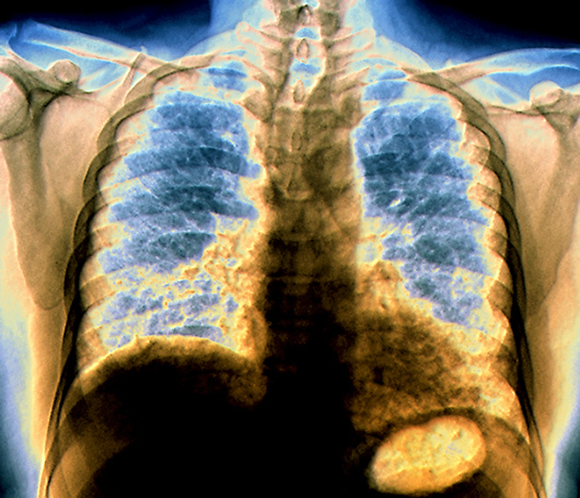

Lung tissue is damaged and replaced with connective tissue. X-ray image of a pulmonary fibrosis patient | Zephyr / Science Photo Library